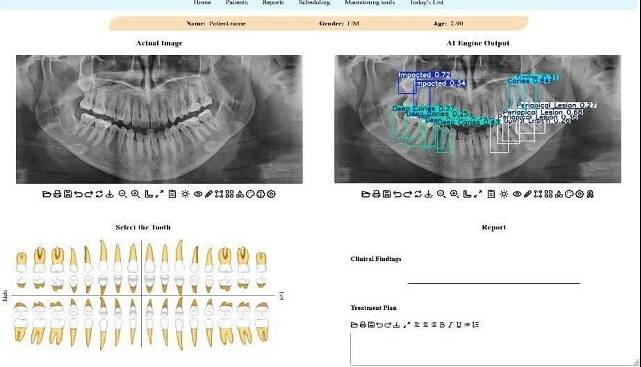

استاد دانشکده مهندسی برق و کامپیوتر دانشگاه تهران با بیان اینکه در این پژوهش جدید محققان تلاش کردهاند تا این چالش را با کمک فناوری حل کنند، افزود: برای این منظور یک سامانه تشخیصی مبتنی بر هوش مصنوعی طراحی شده است که این سامانه، معماری پیشرفته شبکه عصبی به نام YOLOv11 است که آموزش آن بر روی یک مجموعهداده عمومی انجام شده است. این مدل قادر است بهصورت خودکار، محل دقیق ضایعات و ناهنجاریها را در تصویر شناسایی کرده و احتمال درستی تشخیص خود را نیز اعلام کند.

ظروفی یکی از نقاط قوت این پژوهش را کاربردی شدن پژوهش در قالب یک اپلیکیشن وب، عنوان کرد و گفت: یکی از نقاط قوت این پژوهش، کاربردی بودن آن است. این مدل در قالب یک اپلیکیشن تحت وب پیادهسازی شده تا دندانپزشکان و رادیولوژیستها بتوانند به سادگی از آن استفاده کنند. این سامانه با مشخص کردن محل دقیق مشکلات، به پزشک در اولویتبندی و تصمیمگیری سریعتر کمک میکند.

وی همچنین افزایش سرعت و اطمینان در تصمیمگیری بالینی را از دیگر مزیتهای استفاده از این سامانه در تشخیص مشکلات دندانپزشکی برشمرد و افزود: به گفته کارشناسان، بهرهگیری از چنین سامانههایی نه تنها سرعت فرآیند گزارشنویسی را افزایش میدهد، بلکه به عنوان یک ناظر دوم، میتواند با کاهش خطاهای ناشی از خستگی یا حجم بالای کار، دقت تشخیص نهایی را ارتقا دهد و نقش مکملی مؤثر برای متخصصان فک و صورت ایفا کند.